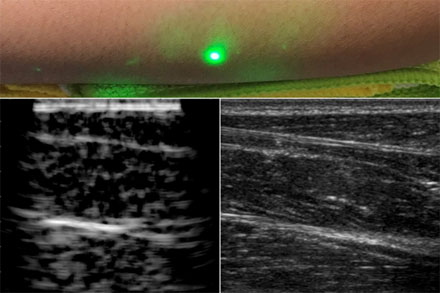

一種新的超聲波技術(shù)利用激光在皮膚下產(chǎn)生圖像,而不像傳統(tǒng)的超聲波探頭那樣與皮膚接觸。新的激光超聲技術(shù)被用來產(chǎn)生一個人類前臂的圖像(左),這也是使用常規(guī)超聲成像(右)。由X.Zhang等人提供。

最后,研究小組利用麻省理工學(xué)院人類實驗委員會批準(zhǔn)的方案,在人類身上進行了第一次激光超聲實驗。在掃描了幾名健康志愿者的前臂后,研究人員制作了他們認為是第一幅完全非接觸式的人體激光超聲圖像。脂肪、肌肉和組織邊界清晰可見,可與使用商用接觸式超聲探頭生成的圖像相媲美。